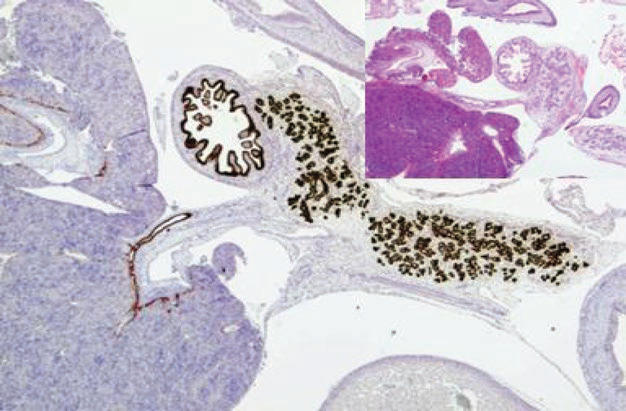

Figure 1. This case is a 12-week embryonic tissue. Immunohistochemistryshows PDX-1 expression in pancreatic ducts, duodenal mucosa, and bile duct mucosa.

When used for tumor diagnosis, PDX-1 is strongly positive in pancreatic endocrine tumors and pancreatobiliary adenocarcinomas, the latter including gallbladder adenocarcinoma and cholangiocarcinoma. PDX-1 weak positivity is also seen in some colorectal adenocarcinomas. Other tumors that may show focal weak positive expression of PDX-1 include prostate cancer, lung cancer, breast cancer, thyroid cancer, liver cancer, splenic tumors, renal cancer, and skin cancer.